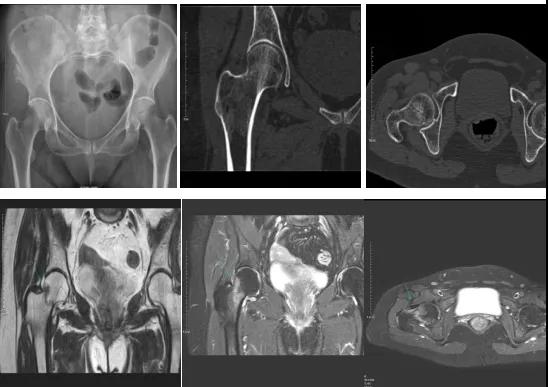

2.CT或MRI檢查。CT是斷面成像,不會出現(xiàn)重疊而導(dǎo)致漏診,同時CT還可以進行多平面的重建,除了發(fā)現(xiàn)X線無法發(fā)現(xiàn)的骨折外,還可以三維直觀的顯示骨折的程度,對臨床治療有指導(dǎo)意義。CT無法發(fā)現(xiàn)骨裂、不全骨折或者骨挫傷,對軟組織的損傷診斷也有局限性,MRI就可以發(fā)現(xiàn)這些損傷。

DR示:右側(cè)股骨頸未見明顯骨折征象。CT右側(cè)股骨頸骨質(zhì)密度不均?;颊唧w征明顯,為明確診斷,行MRI檢查。MRI示:右側(cè)股骨頸T1WI呈低信號,脂肪抑制序列呈高信號;提示右側(cè)股骨頸隱匿性骨折。